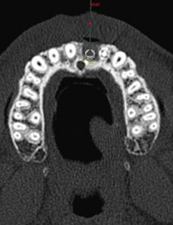

抜歯後CT 撮影 1

3D画像を構築する唇側の骨欠損が広範囲に及んでいる

理想的な位置に埋入すると骨が不足する